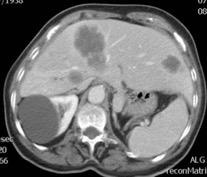

Absceso secundario a perforación de carcinoma. 3-4%. En flexura esplénica puede tener absceso subfrénico o empiema.

Empiema pleural secundario a carcinoma de la flexura esplénica (masa visible)

Lian R et al. Empyema caused by a colopleural fistula. Medicine (Baltimore) 2017/Osada T,, et al. Thoracic empyema associated with recurrent colon cancer: report of a case and review of the literature. Dis Colon Rectum 2001